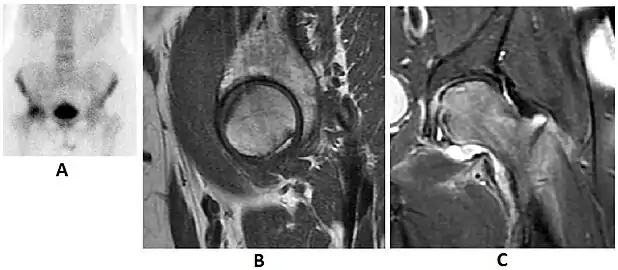

Radiological signs of transient osteoporosis of the hip include localized osteoporosis of the femoral head and neck (Figure 8). Nevertheless, final diagnosis has to be made with MRI to differentiate it from avascular necrosis and from insufficiency or stress fractures of the femoral head or neck. In case of AVN, radiographs can only demonstrate delayed or advanced signs. Staging according to Ficat classification ranges between normal appearance (stage I), slight increased density in the femoral head (stage II), subchondral collapse of the femoral head with or without “crescent” sign (stage III), and advanced collapse with secondary osteoarthritis (stage IV). In the case of stress or insufficiency fractures X-ray sensitivity has been proven to be much lower than MRI, which is currently the gold standard.[1]

Figure 8:

X-ray of a patient with transient osteoporosis of the left hip showing osteoporosis.[1]

Coronal stir imaging in transient osteoporosis, showing diffuse edema.[1]

Scintigraphy (A), sagittal T1 (B), and coronal PD fat sat of a patient with a subchondral fracture of the femoral head with convex shape to the articular surface.[1]

Coronal T1 of a patient with avascular necrosis of the femoral head.[1]

Intra-articular osseous causes of pain include several conditions: avascular necrosis (AVN), transient osteoporosis of the hip (TOH), tumors, and stress or insufficiency fractures. All these entities may present with a pattern of bone marrow edema characterized by decreased signal intensity on T1 weighted images and increased signal intensity on fluid sensitive sequences, such as fat saturated T2-weighted or STIR images. When there is no evidence of a focal lesion associated with the edema pattern, TOH is suspected. When a band of low intensity is seen inside the edematous area, the shape and length of this band become important. It is generally convex to the articular surface in the case of subchondral stress or insufficiency fractures, whereas it is concave, circumscribing all of the necrotic segment, in cases of AVN. When doubts do persist, gadolinium-enhanced MRI tends to show that the proximal portion beyond the band is enhanced in fractures but is not in AVN.[1]

MRI has been shown to have 100% sensitivity and specificity in prospective studies of occult hip fractures. These fractures were diagnosed by bone marrow edema and a low signal fracture line, mainly on T1 or T2 weighted images (Figure 10).[1]

Bone scanning in people with hip pain can be complementary to other imaging studies, mainly in indeterminate bone lesions to clarify whether it is an active lesion with abnormal radiotracer accumulation. Nevertheless, MRI has replaced scintigraphy in the diagnosis of most of these conditions. An example is stress or insufficiency fractures: increased uptake is usually present in around 80% of fractures within 24 h, and 95% of fractures reveal activity by 72 h following trauma, showing an overall sensitivity of 93% and specificity of 95%. MRI is superior to bone scans in terms of sensitivity (99%-100%) and specificity (100%). Moreover, a bone scan does not provide detailed anatomical location of the fracture, and further imaging is usually required.[1]